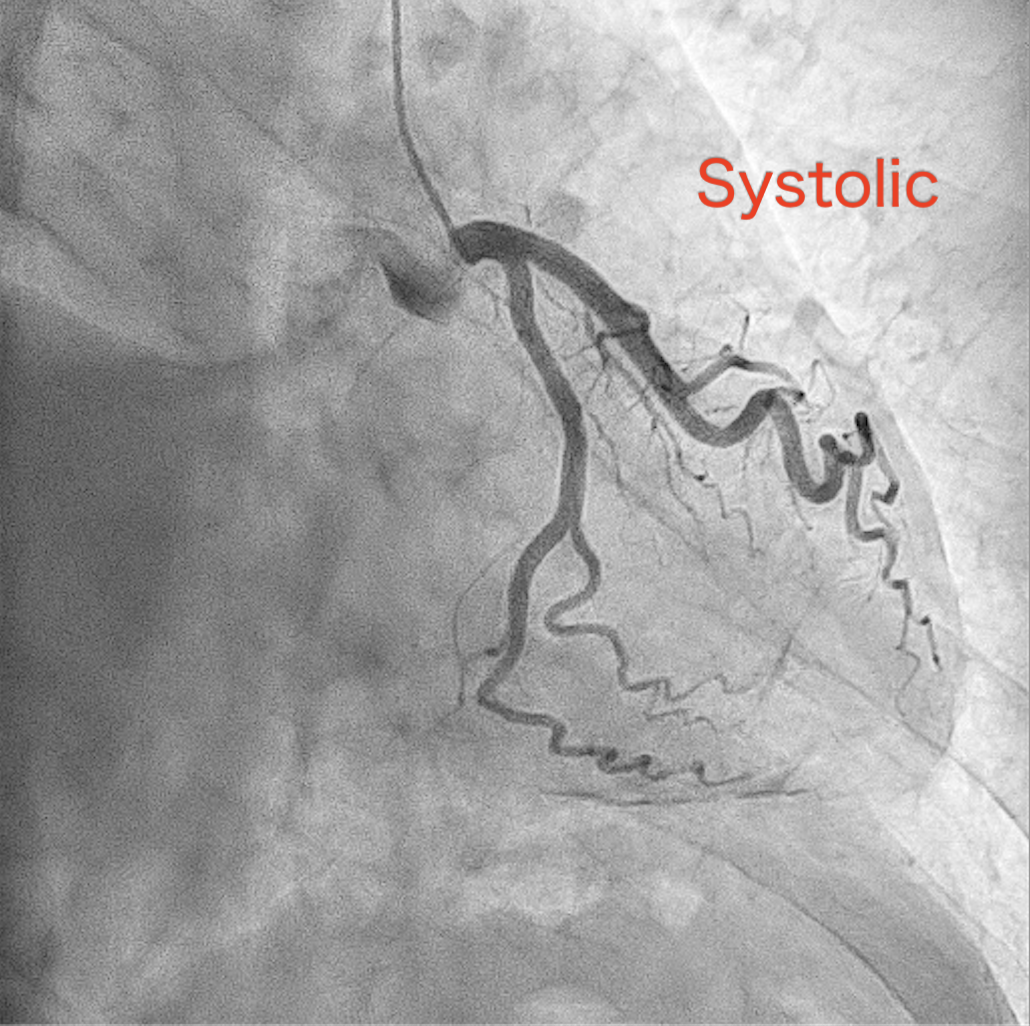

Coronary angiography revealed a distinctive finding in which the vessels and branches covering mid- to apical region of the left ventricle did not completely move in conjunction with the cardiac cycle, while those covering basal-part myocardium and running along left atrioventricular groove remain synchronized with the heart motion. This unusual finding was explained by the hard-and-fixed pericardium firmly adhered to the myocardium constraining the pulsation of the relevant part of the coronary tree. (Fig7-8) To obtain a more detailed anatomical and functional assessment, cardiac computed tomography (CT) was performed. The CT study further confirmed the absence of the usual counterclockwise rotational motion of the left ventricular apex during systole, a finding that was in complete agreement with the previously observed coronary angiographic pattern. In addition, the imaging revealed impaired diastolic filling of both ventricles, diffuse pericardial thickening, and signs of pericardial adherence, all consistent with the diagnosis of constrictive pericarditis.